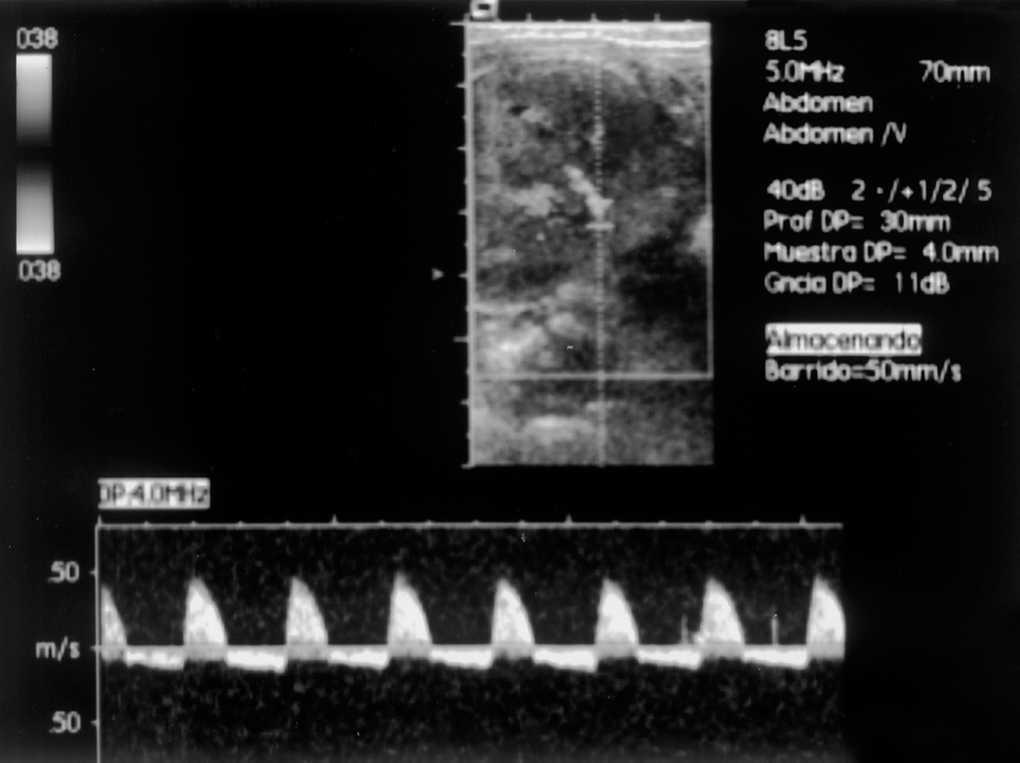

Figura 2. Estudio eco-Doppler de arteria renal derecha con inversión del flujo diastólico.